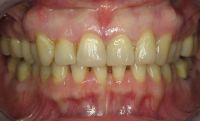

Na de behandeling met composiet

Door het composiet is er weer een dikke, stevige laag ontstaan aan de binnenzijde die niet snel zal afbreken. De tanden zijn hierdoor ook weer verlengd.